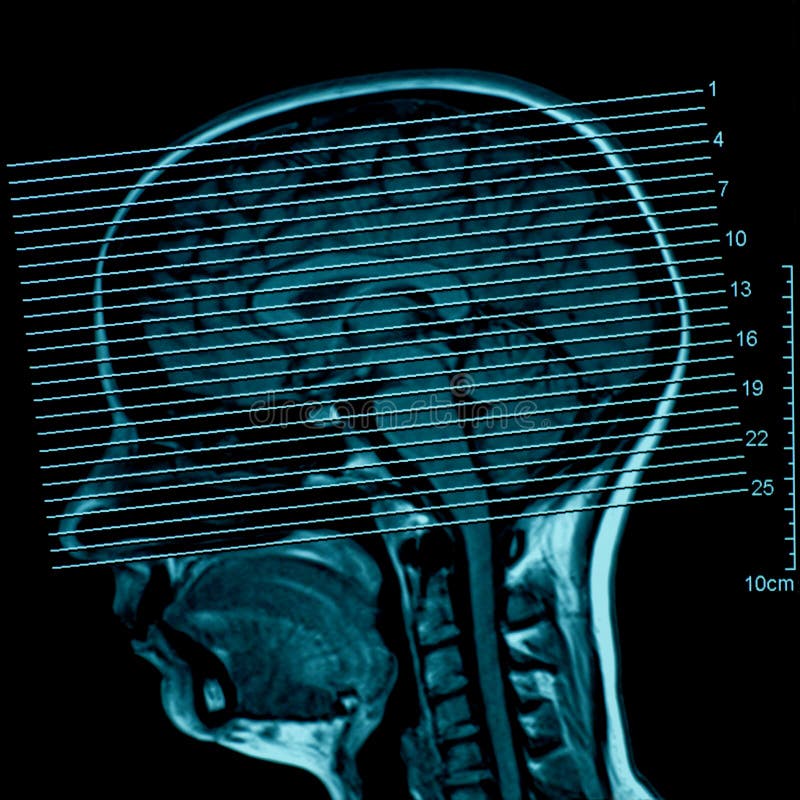

Lista muestra hermosas imágenes de resonancia magnética cerebral normal y anormal dinosenglish.edu.vn para que puedas explorar más en detalle.

Engineer Team : RESONANCIA MAGNETICA Magnetic Resonance Imaging – Clinical Images Hallazgos por resonancia magnética cerebral de nuestro paciente. M, 21 … Imágenes por resonancia magnética anormales como predictoras de mal … Imágenes por resonancia magnética anormales como predictoras de mal … Lesiones en resonancia magnética (RM) del encéfalo y la médula espinal … Pin en Resonancia Magnética del Encéfalo A) Resonancia magnética cerebral (RMC) mostrando infartos en … Caso 1: Edema cerebral visualizado mediante RM. (A) Secuencia T1 plano … Rascacielos dormir pasta tac y resonancia diferencias retrasar … Pin on Apuntes de Enfermería y T.C.A.E Resonancia magnética cerebral secuencia T2, que muestra lesión … Meningitis aguda en la enfermedad de Behçet | Reumatología Clínica Resonancia magnética coronal normal del cerebro Fotografía de stock – Alamy Imágenes de resonancia magnética, la imagen de la cabeza en diferentes … Resonancia magnética cerebral A) protocolo T1 sagital (Caso 1). Se … Resonancia magnética cerebral. Secuencia T1 corte sagital. Atrofia … Resonancia magnética de cerebro, cortes axiales, secuencias T2. Señal … Resonancia magnética de cráneo. A y B) Cortes axiales FLAIR … Resonancia magnética (RM) de cerebro, corte axial ponderado en T2: la … RM cerebral: Interpretación paso a paso | Kenhub Resonancia magnética de cerebro, cortes axiales, secuencias T2. Señal … De Resonancia Magnética De Cerebro Foto de archivo – Imagen de arteria … Top 107+ Imagenes de resonancia cerebral normal – Destinomexico.mx -Imagen por resonancia magnética del cerebro. a) Cortes sagital y axial … resonanCia magnétiCa Cerebral donde se observa hiperintensidad a nivel … MRI (Imagen de resonancia magnética) – Tomografía computarizada de la … Meningioma – NCI Imágenes por resonancia magnética coloreadas del cerebro sano del … Resonancia magnética cerebral en secuencia FLAIR, que muestra lesiones … Contraste resonancia magnetica cerebral – senturinthegreen Relación de los espacios de Virchow-Robin con la enfermedad de … Gliomatosis cerebral – Instituto Nacional del Cáncer Pin en Neurology. Recomendaciones para la utilización e interpretación de los estudios de … Fotografía De La Proyección De Imagen De Resonancia Magnética Del … atmósfera Dirigir Cumplir anatomia resonancia magnetica Desarrollar … Pin en #MEDICINA,#SALUD Resonancia magnética de la nasofaringe De Resonancia Magnética De Cerebro Foto de archivo – Imagen de polilla … Atrofia cortical global de predominio parietal en la Resonancia … Resonancia magnética cerebral | Download Scientific Diagram Neuroblog: Resonancia magnética cerebral en la trombosis crónica de … De Resonancia Magnética De Cerebro Imagen de archivo – Imagen de … ¿Cuáles son los riesgos de la resonancia magnética? – Integra Salud … Resonancia magnética cerebral al decimocuarto día de ingreso: área … Resonancia magnética. Corte axial mostrando área infartada en el … Resonancia magnética cerebral del paciente AV evidenciando lesiones en … -Ressonância magnética de encéfalo mostrando múltiplas imagens … Resonancia magnética cerebral secuencia FLAIR (Fluid Attenuated … Resonancia magnética cerebral con protocolo de epilepsia, en sección … Resonancia magnética cerebral en corte sagital. Se observa una evidente … Resonancia magnética craneal en la que se evidencian lesiones … Logran visualizar el cerebro a detalle más completo tras una resonancia … Así decide el cerebro la severidad de un castigo De Resonancia Magnética De Cerebro, Imagen de archivo – Imagen de … A) Resonancia magnética cerebral; Secuencia Tof: oclusión de arteria … Un estudio asocia la ansiedad con la aparición rápida del Alzheimer IMÁGENES DE 18 F-PR04.MZ PET FUSIONADA CON RESONANCIA MAGNÉTICA … Imágenes por resonancia magnética anormales como predictoras de mal … Tumores de la región pineal – Instituto Nacional del Cáncer Epilepsia: una historia de voces y fantasmas | Neurología Contribución de las imágenes de resonancia magnética por tensor de … Resonancia magnética secuencia T2 plano coronal de quiste epidermoide … Resonancia Magnética Cerebral del paciente: a. Aumento de… | Download … Resonancia magnética cerebral 2022 Síndrome de hemiconvulsión-hemiplejía-epilepsia. Seguimiento de un caso … Enfoque Radiologico: La resonancia magnética permite detectar lesiones … Resonancia magnética craneal T1 con contraste que muestra angiomatosis … guidewiz – Blog Resonancia magnética cerebral, secuencia SWI. Ribete hipointenso en la … resonAnCiA mAgnétiCA de ColumnA Con gAdolinio. Corte sAgitAl en t1 de … SEMANA 12: FUNDAMENTOS DE RESONANCIA MAGNÉTICA NUCLEAR. INDICACIONES Y … DIAGNÓSTICO DE ESCLEROSIS MÚLTIP Magnetic resonance imaging of the brain – Alchetron, the free social … Resonancia magnética de órbitas | Instituto Radiológico Dr. E Castillo Alteración de la marcha en un paciente post-trasplante hepático Resonancia magnética cerebral de un paciente sano (Ay B) y paciente que … Utilidad de la resonancia magnética craneal para el diagnóstico de la … Resonancia Magnética Del Cerebro El Tumor Cerebral Foto de stock y más … De Resonancia Magnética De Cerebro Imagen de archivo – Imagen de … ABDALLA RADIOLOGIA: NEURINOMA ACUSTICO Atrofia cortical global de predominio parietal en la Resonancia … Resonancia Magnética : Producción de la imagen MRI Brain Scan — Stock Photo © Bunyos30 #18724051 Mri (imagen de resonancia magnética) Monitor con imagen de captura de … Tomografía computarizada vs resonancia magnética: diferencia y … Tumores Cerebrales – Unidad de Neurocirugía RGS Resonancia magnética de la columna, sección sagital. Observe los discos … La resonancia magnética, una técnica imprescindible en el diagnóstico … Perfusión Cerebral por Resonancia Magnética | ¿Qué es? ¿Necesita Contraste? Resonancia Magnética Cerebro A: resonancia magnética, T2 coronal preoperatoria; se observa lesión en … Resonancia magnética cerebral — Foto de stock © Bunyos30 #27340623 La resonancia magnética se perfila como detector de mentiras | Futuro … Resonancia magnética cerebral en T1 con gadolinio, cortes axial (a … MRI brain : show brain tumor at right parietal lobe of cerebrum — Stock … NEUROIMÁGENES EN ENFERMEDAD DE PARKINSON: ROL DE LA RESONANCIA …